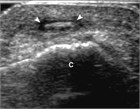

Subcutaneous foreign bodies can be the result of projectile injuries (e.g., grinding metals) or due to falls with subsequent wound contamination. Imaging, location, and removal are discussed, with an emphasis on a balanced approach between risk of removal vs. risk of retention.

ultrasound-guided techniques